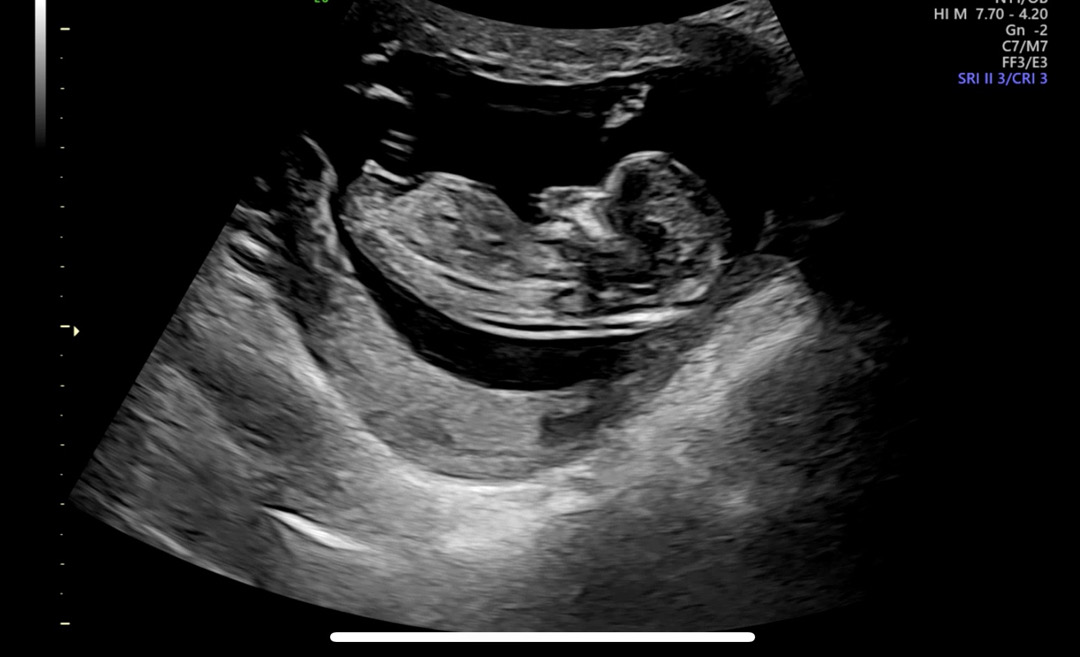

12주 4일차 각도법 문의드려요!

아들인지 딸인지 알수있을까요..???

딸 같아요!

딸같아용 ㅎㅎ

딸에 한표요 ㅎㅎ